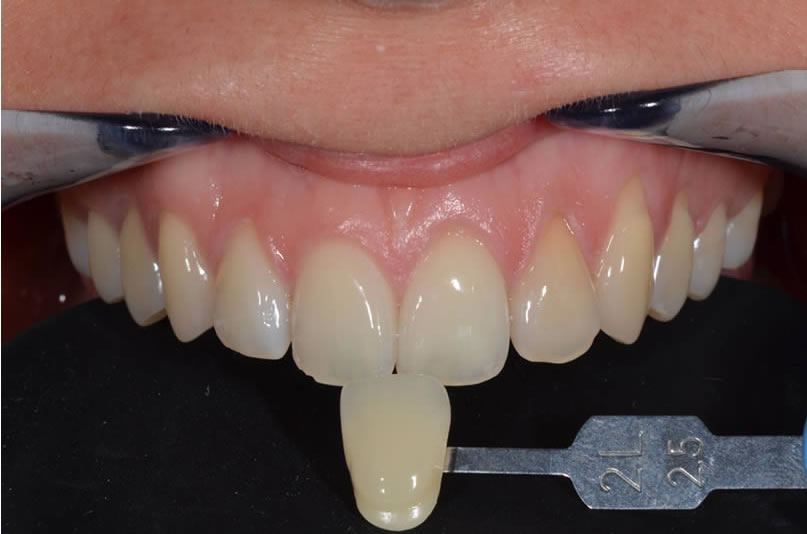

Les recommandations actuelles sont d’utiliser une barrette de référence du teintier au minimum pour donner au prothésiste un élément de comparaison.

Il faudra faire attention au changement de teinte lié à la déshydratation : une dent déshydratée paraîtra plus claire. Il est donc conseillé de prendre la teinte en début de séance et d’attendre la réhydratation de la dent avant de valider le résultat esthétique final.

1- Mesure au teintier électronique Easyshade ;

2- Contrôle manuel au teintier shadeguide/ 3Dmaster ;

3- Photo avec échantillon de teinte (lumière naturelle et polarisée) ;